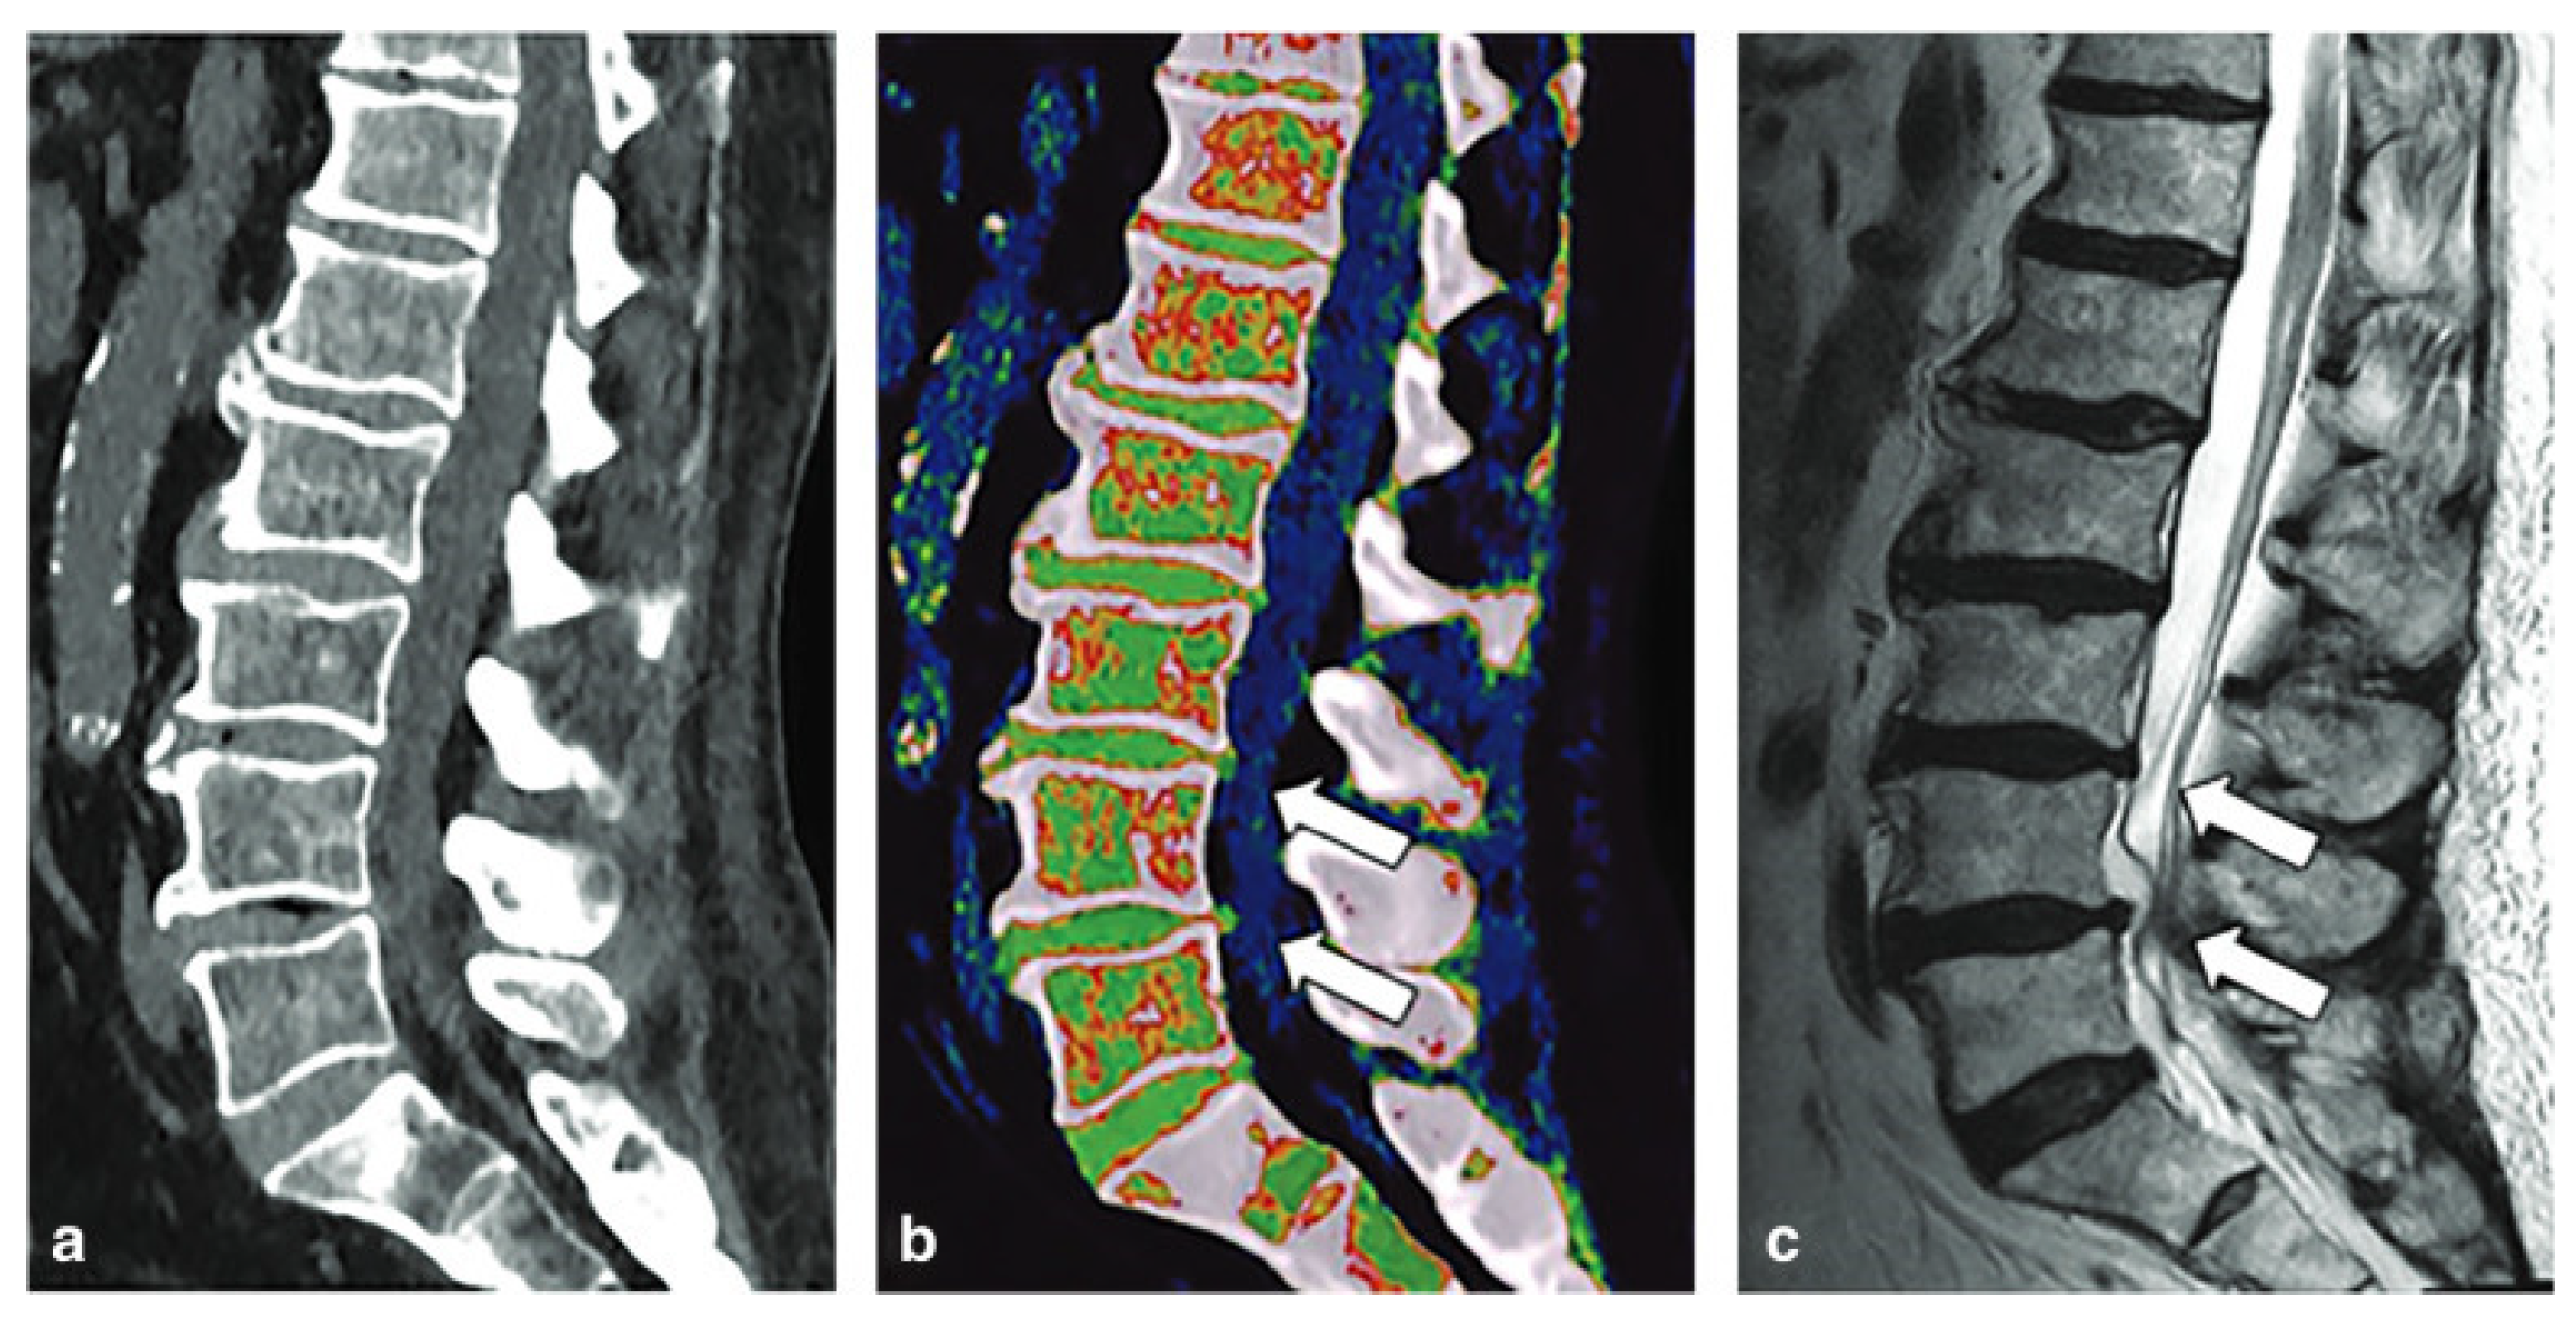

- Cavallaro, M.; D’angelo, T.; Albrecht, M.H.; Yel, I.; Martin, S.S.; Wichmann, J.L.; Lenga, L.; Mazziotti, S.; Blandino, A.; Ascenti, G.; et al. Comprehensive comparison of dual-energy computed tomography and magnetic resonance imaging for the assessment of bone marrow edema and fracture lines in acute vertebral fractures. Eur. Radiol. 2022, 32, 561–571. [Google Scholar] [CrossRef]